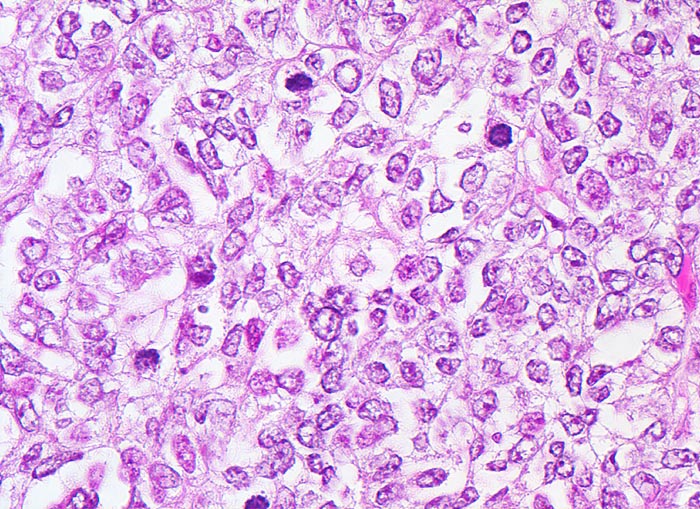

Endometrioide Karzinome bestehen aus tubulären Drüsen, welche von einem mehrreihigen Epithel ausgekleidet werden. Schleim ist meist nicht oder nur apikal in den Zellen vorhanden. Die Ausdehnung der soliden Areale und die zytologischen Atypien bestimmen den Differenzierungsgrad (low-grade versus high-grade). Metaplastisches Plattenepithel findet sich häufig in endometrioiden Karzinomen und hilft bei der Abgrenzung von anderen Subtypen. Das endometrioide Karzinom kann sich innerhalb von Adenomyoseherden im Myometrium entwickeln (> 4482). In diesen Fällen kann die Bestimmung der Infiltrationstiefe erschwert sein.

• Tumordrüsen ausgekleidet von mehrreihig angeordneten Tumorzellen mit hyperchromatischen polymorphen längsovalen Tumorzellkernen mit zahlreichen Mitosen. Die Morphologie der Tumordrüsen erinnert an proliferatives Endometrium.